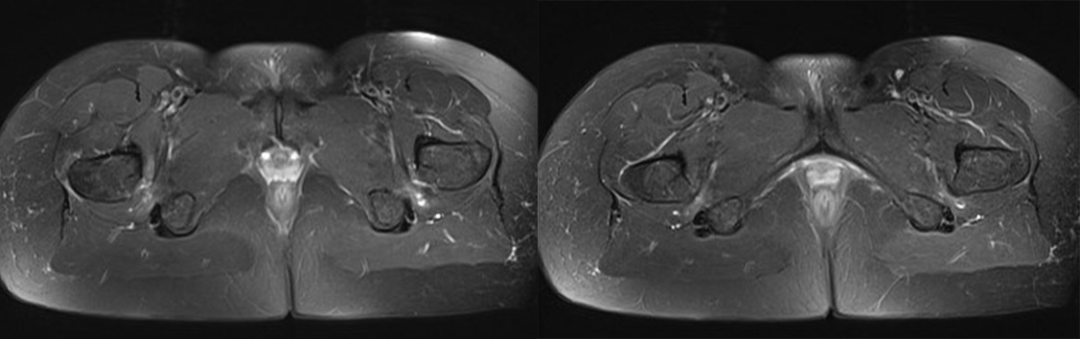

1. 坐骨股骨间隙变窄,坐骨股骨间隙是坐骨结节外侧骨皮质到股骨小转子内侧骨皮质的最窄距离,正常坐骨股骨间隙正常人群组为 23±8 mm,若间隙﹤15 mm 可视为狭窄。

2. 股方肌间隙变窄,股方肌间隙是股方肌通过的最窄间隙,其后内侧边界是腘绳肌肌腱止点的外上表面,前外侧边界是髂腰肌肌腱或股骨小转子的后内侧表面,测量这两个边界之间的最短距离。正常股方肌间隙人群组为 12±4 mm,若间隙﹤8 mm 可视为狭窄。

3. 股方肌以位于坐骨股骨间隙最狭窄处的肌腹为中心出现水肿信号或挤压变形。

测量方式:坐骨-股骨间隙测量 两侧相比右侧坐骨-股骨间隙缩小

股方肌位于狭窄处出现水肿